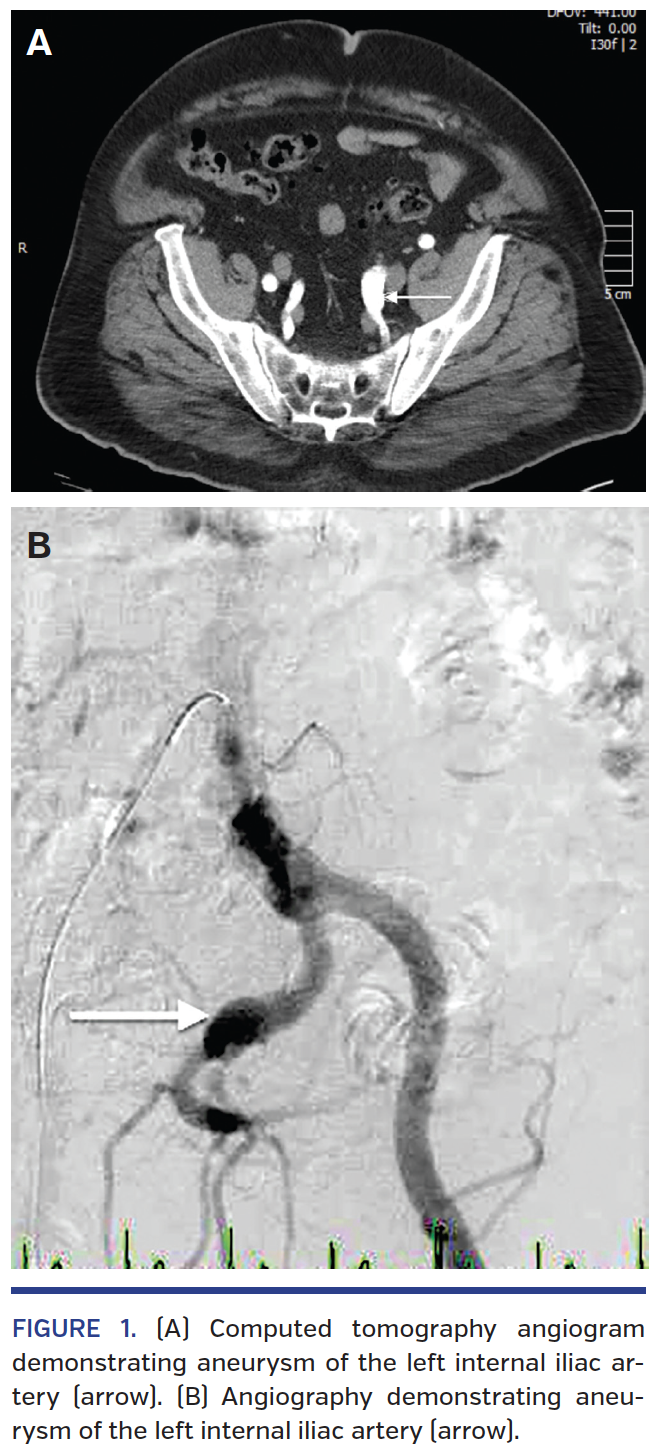

Overall design. We report our experience with 8 patients who underwent endovascular treatment of their IIAA. Each patient underwent abdominal aortic aneurysm (AAA) screening ultrasound (US) or computed tomography (CT) imaging for suspected or known AAA that revealed IIAA (Figure 1A). The decision was made to occlude the IIAAs since it has been established that the natural progression of IIAAs is continual expansion with subsequent increase in risk of rupture.

Preembolization procedure. Angiography and embolization were performed in a cardiac catheterization suite. All patients received intravenous conscious sedation using midazolam and fentanyl. Each patient was anticoagulated with heparin to maintain an activated clotting time (ACT) of 200-250 seconds. All patients were accessed using a femoral approach via the ipsilateral or contralateral femoral artery. The access site was prepped and draped in the usual sterile fashion. A 7 Fr vascular introducer sheath (Terumo Medical) was placed in the femoral artery for access. Contrast-enhanced angiography was performed in the catheterization lab, providing both intraarterial subtracted and unsubtracted imaging of the iliac arteries (Figure 1B) using a 5 Fr pigtail catheter (Cook Medical). Anteroposterior (AP), contralateral oblique, and lateral imaging views were obtained as necessary throughout the procedures.